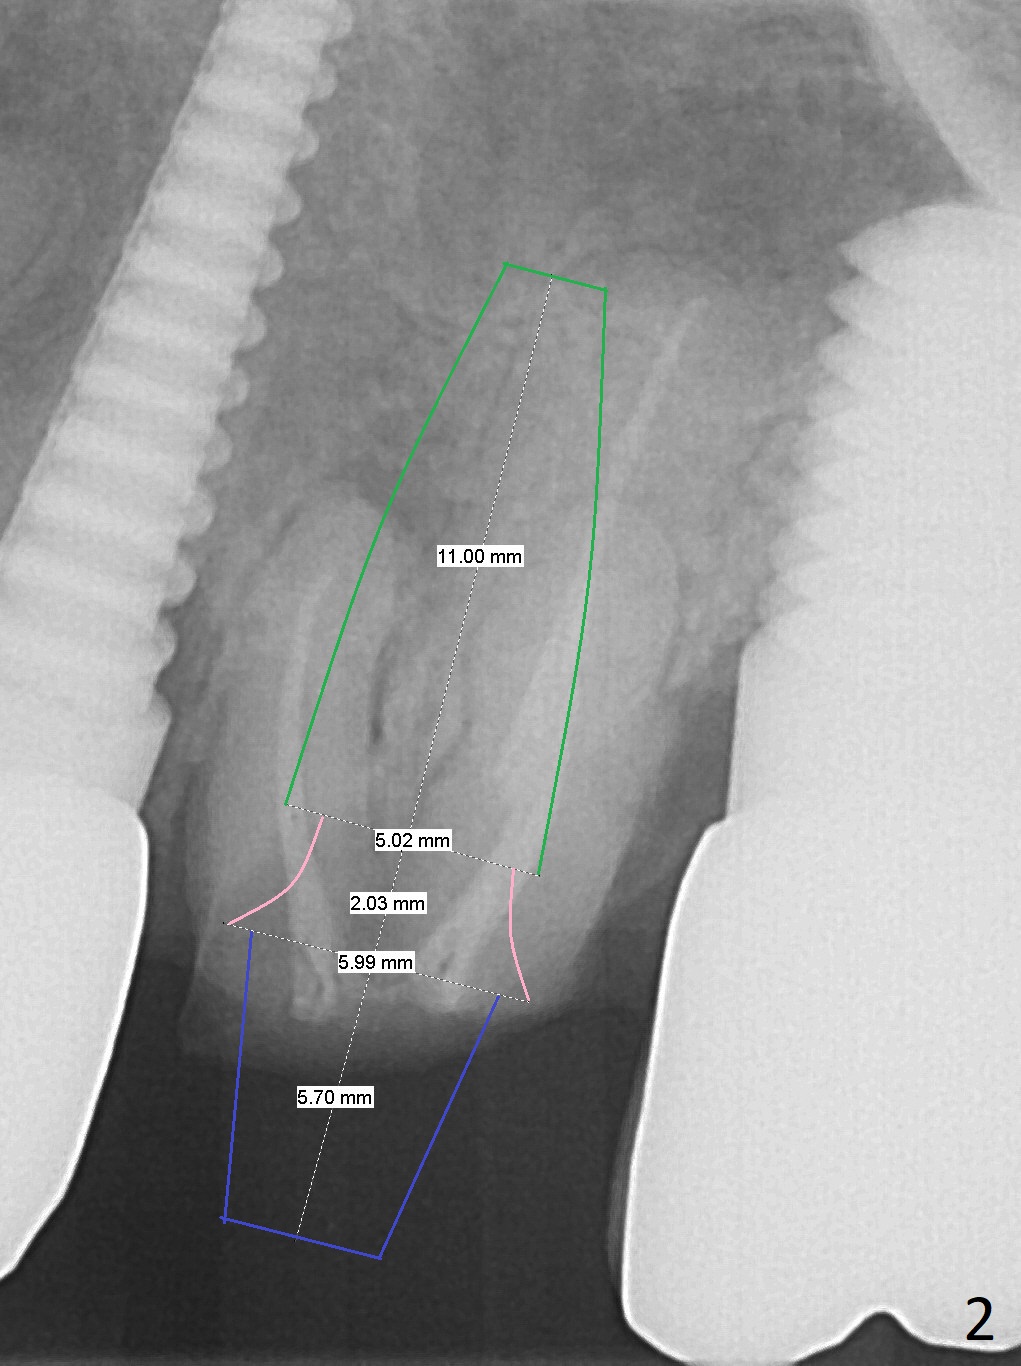

A 70-year-old woman fractures the crown at #14 (Fig.1). A 5x11 mm implant will be placed at the septum (Fig.2). Osteotomy depth can be determined using bony (Fig.3 with stopper) or gingival (Fig.4,5 with vision) landmark. The CT was taken 5 years earlier. Sagittal (Fig.6) and axial (Fig.7) sections confirm suitability of the 5x11 mm implant for the site. Prepare surgical handpiece for sectioning the tooth for extraction. After drills, use Magic Expanders for sinus lift. Place Vanilla Graft prior to dummy implant(s). A bone-level implant crown may be easier to be repaired if the proximal contact is not ideal.